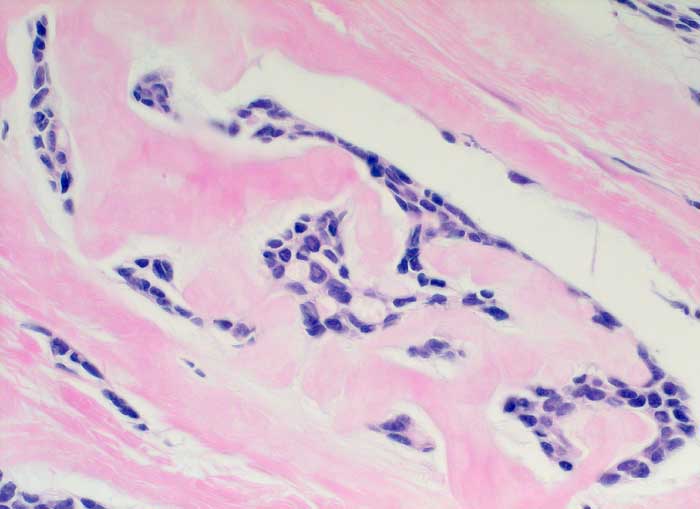

Adenoidzystisches Karzinom

Dichtes amyloidartiges Stroma umschliesst residuelle zylindromatöse Knoten.

Adenoidzystische Karzinome kommen vor allem im Bereich der Speicheldrüsen vor, treten aber auch in anderen Organen auf. Sie machen weniger als 0.1% - 0.2% der Mammakarzinome aus.